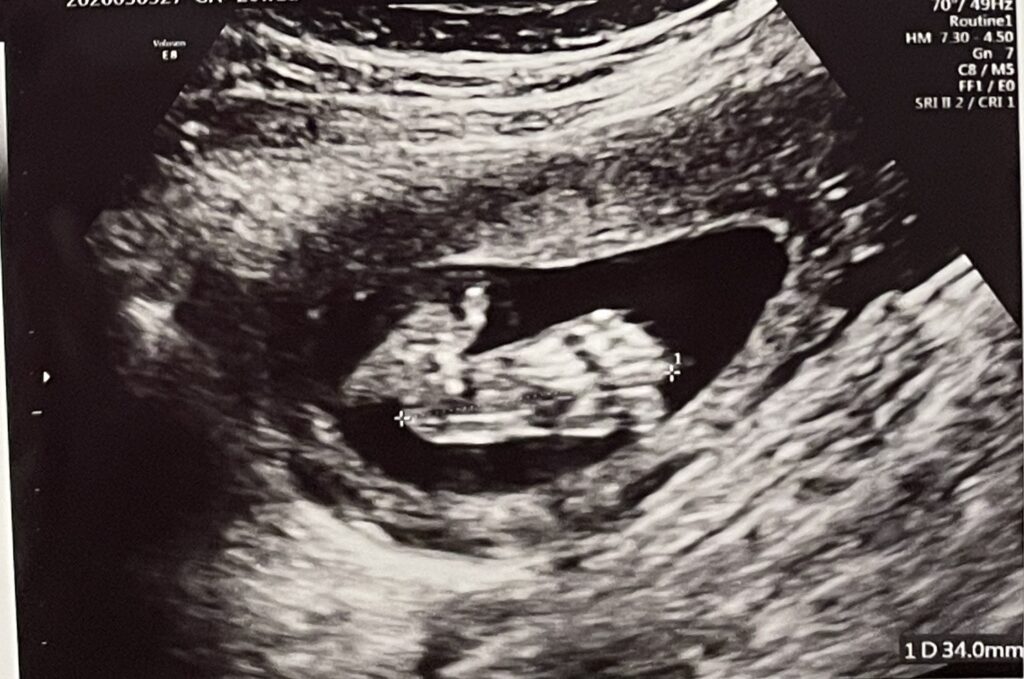

赤ちゃんの内臓や身体のパーツを拡大してチェックしたり、心臓がきちんと分かれているかなどを見たり、心音を聞いたり、色々なパーツのサイズをはかったりしていました。

先生のエコーでの検査が一通りおわった段階で、エコーをわたしに見せながらお顔や身体のパーツを見せてくれたり、心音を聞かせてくれたりしました。

妊娠20週(妊娠6ヶ月)赤ちゃんの性別発覚

女の子でした!女の子はおまたの間に、「コーヒー豆」や「木の葉マーク」と呼ばれる印が目印だそうです。

女の子と言われたけど生まれたら男の子だった!というのはたまに聞く話ですが、この日は体制もよかったためか先生によると「前も下もすっきりしているので、今のところは女の子だと思っていいですよ」とのことでした。